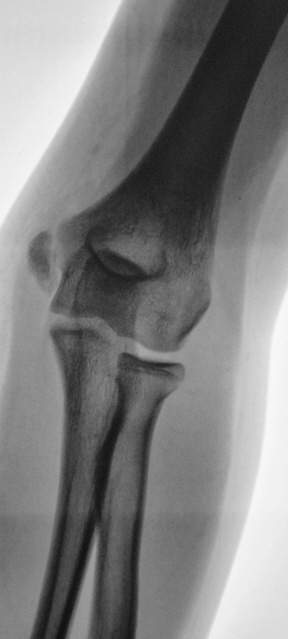

Конечно, Петрович - Вы правы. Формально можно предположить апофизеолиз локтевого отростка, с учетом неравномерности ширины "зоны росткового хряща". Но из-за болевого синдрома, классическую "строго боковую" лаборантам произвести не удалось.

Здесь не хватает боковой проекции здоровой руки. Больная же в боковой проекции снята вполне удовлетворительно.

На здоровой руке обычная зона роста, на травмированной зона роста очень расширена. Это эпифизеолиз.

То есть стало понятно, что это перелом. Лучше - прооперировать